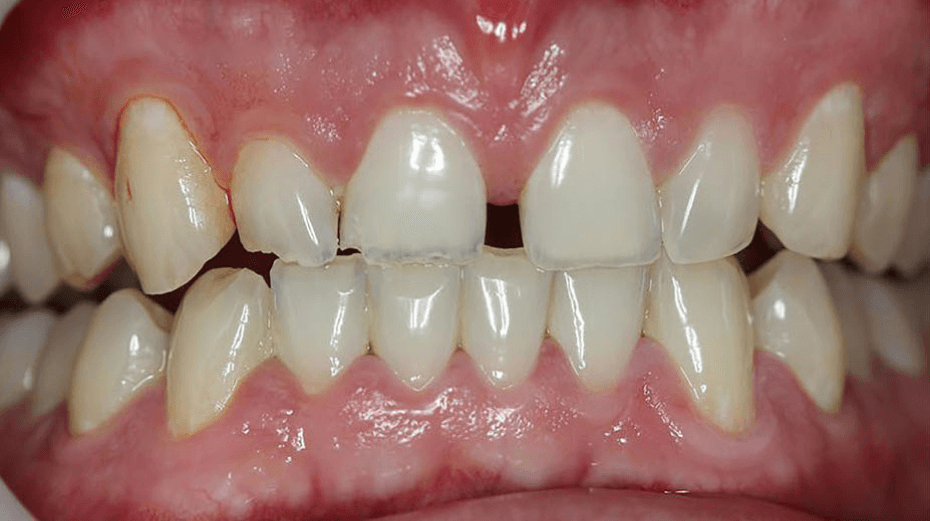

Bez obzira muči li vas problem nejednolike boje zubi, preveliki razmak između zubi, nedostatak ili okrhnuti zub, nepravilan oblik ili pak veličina zuba, zubne ljuskice i krunice idealno su rješenje za vas!

Zubne ljuskice tanki su, individualno izrađeni keramički listići koji se cementiraju na prednju površinu zuba te korigiraju njegove nedostatke kao što su oblik, boja, veličina ili razmak između zubi.

Prilikom postavljanja ljuskica potrebno je odstraniti minimalan sloj zubne cakline što predstavlja jedan od glavnih razloga zašto se mnogo ljudi odlučuje upravo za njih. Osim toga, neinvazivna su i dugotrajna metoda koja ne ostavlja nikakve posljedice na zubno meso.

02. Zubne krunice

Zubne krunice protetski su nadomjestak koji imitira oblik, veličinu i boju zuba u slučajevima kada je tom istom zubu ugrožena čvrstoća.

Zubne krunice koriste se kod oštećenja koja se ne mogu popraviti ispunom, kod zuba oslabljenog karijesima te zuba s velikim oštećenjima. Odlično su rješenje u vidu povratka izgubljene funkcije zuba ili popravljanja njegove estetike.